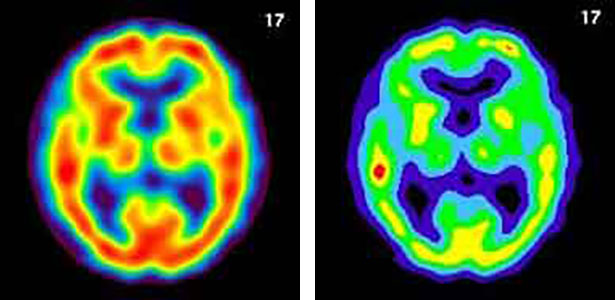

脳血流シンチグラフィ

脳の血流状態を画像化します。

脳血管の塞栓(脳梗塞)や血管の狭窄、認知症、脳炎などに適用されます。

放射性医薬品が注入されたその瞬間の脳血流分布を画像化するため、脳梗塞の評価はもちろん、脳外科手術前の「血管遮断時の血流分布」の評価などが可能です。また、「一定時間内にどれぐらいの血液が脳に流れたか」を調べることでアルツハイマー病などのように脳全体の血流量が減少する疾患の検出も可能です。